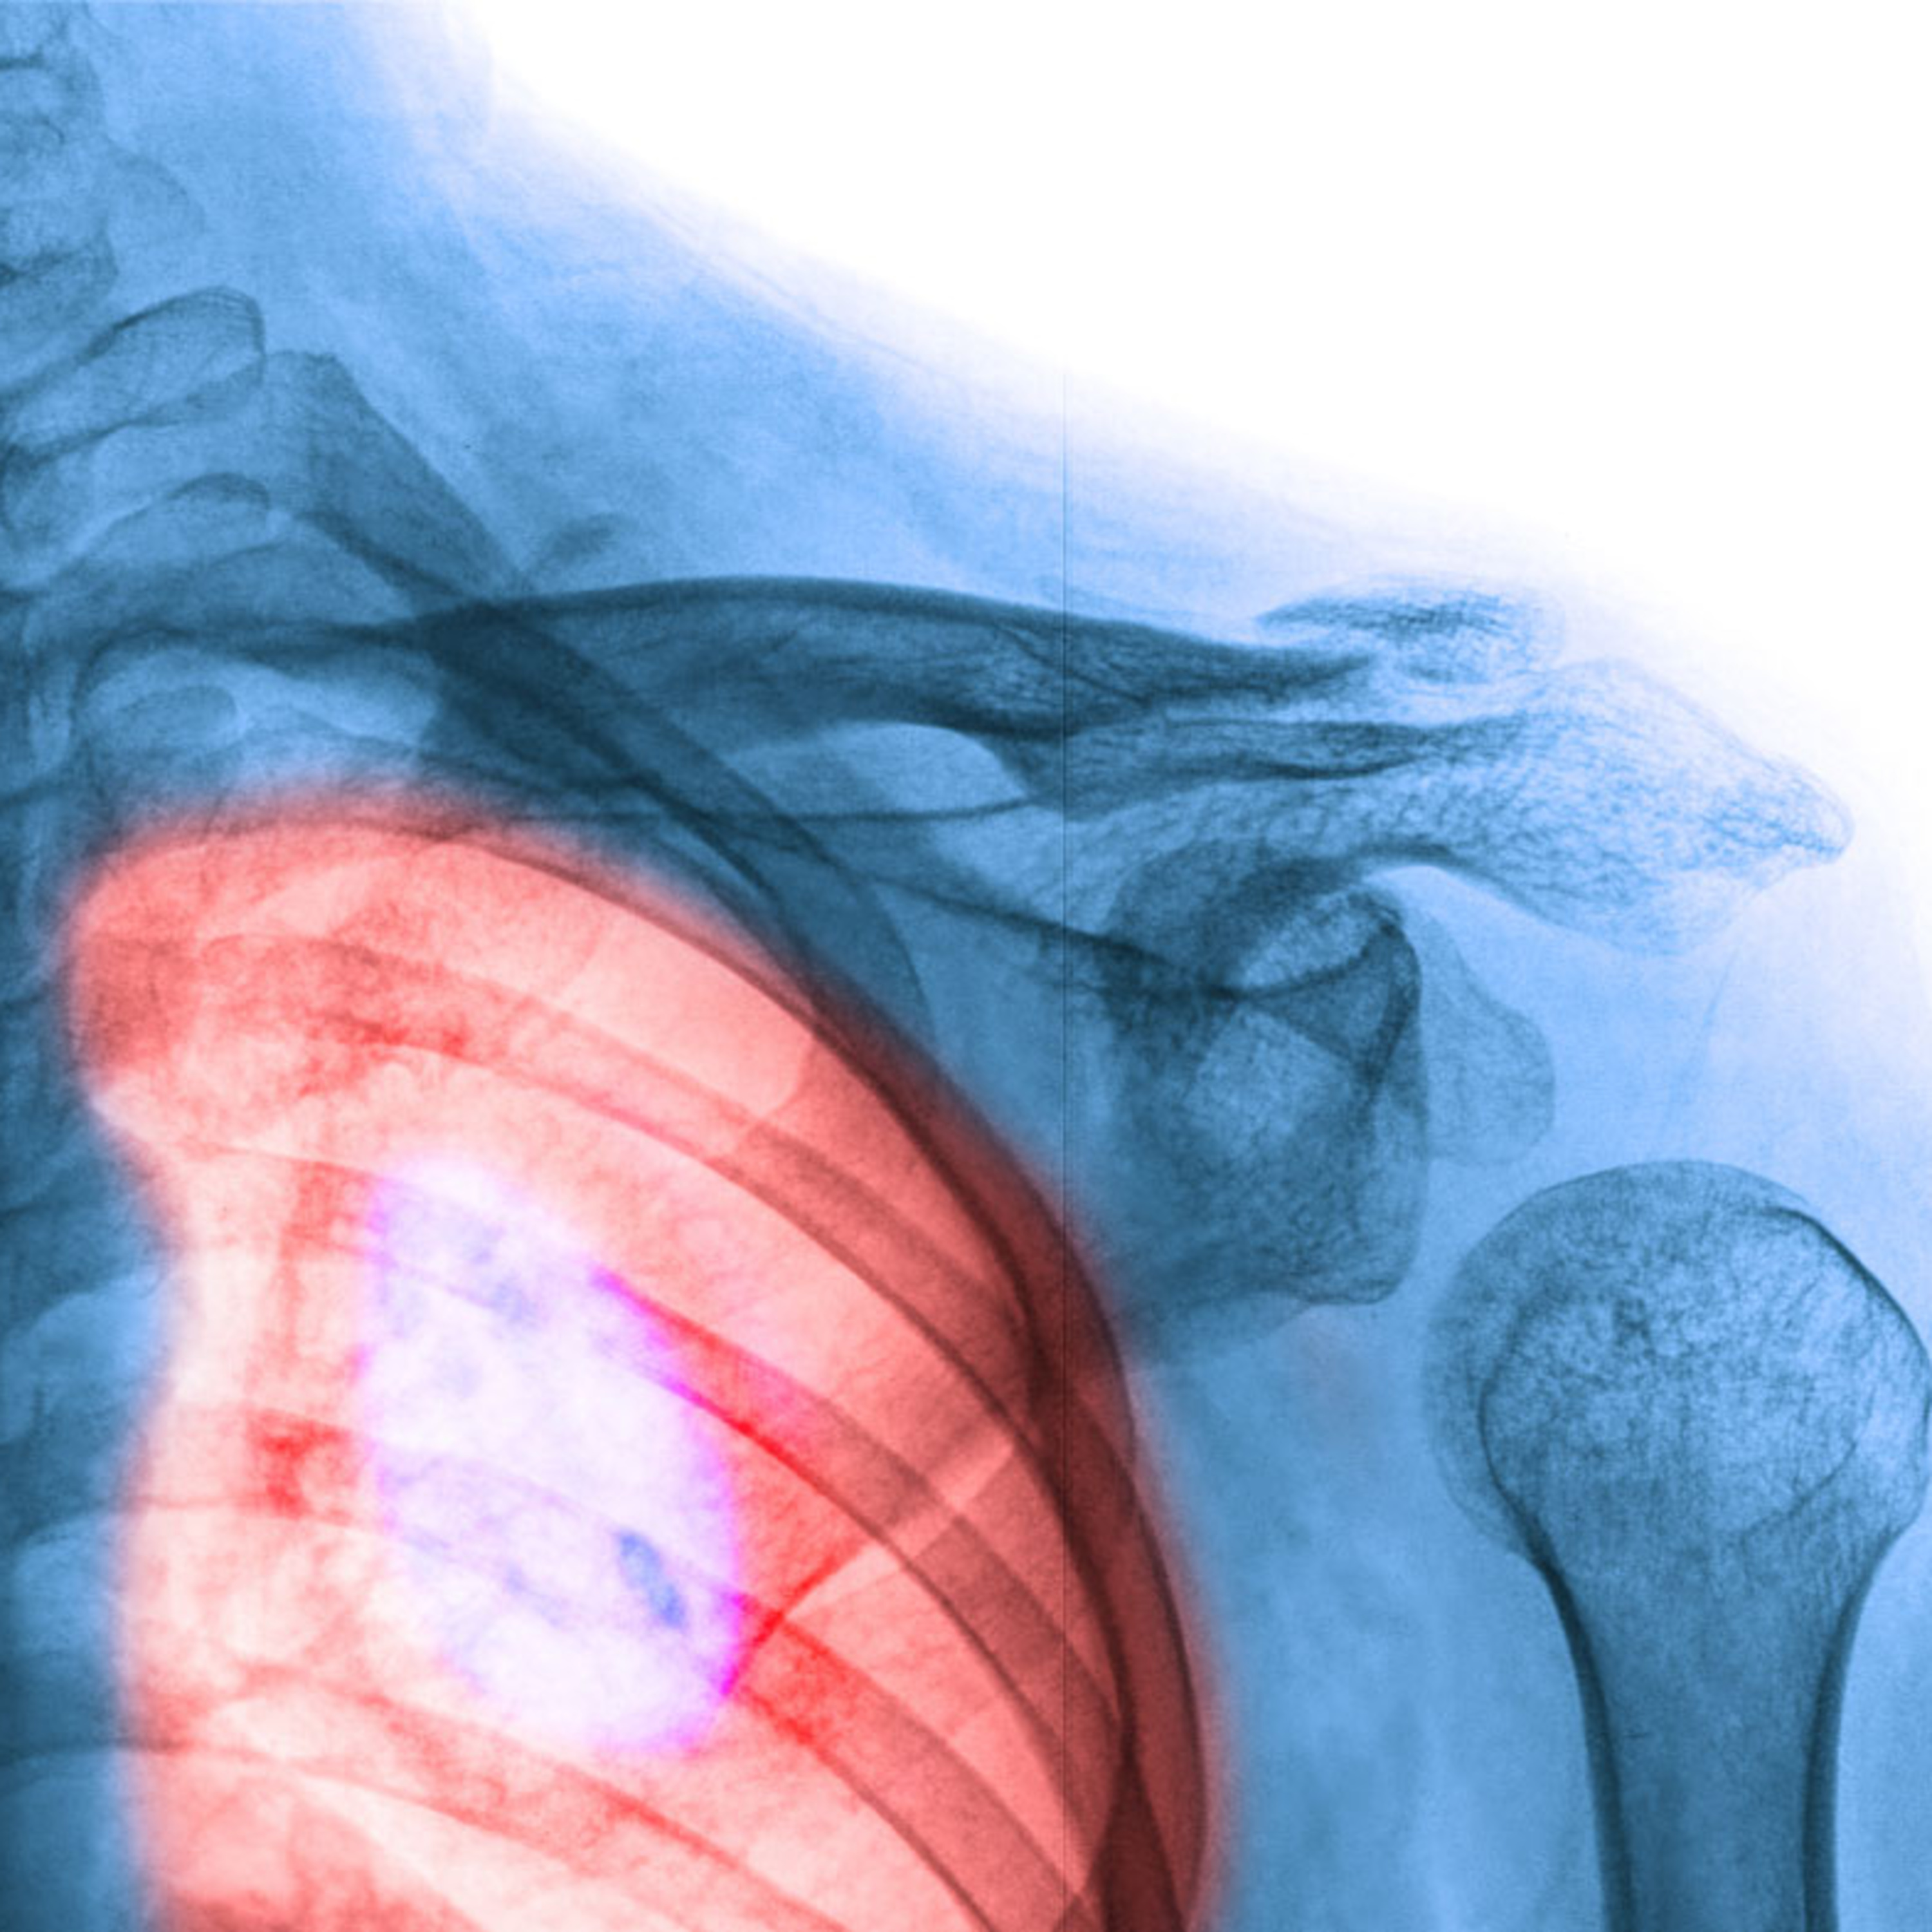

Depending on what type of cancer exists, there are different treatment options. But one of the biggest factors that determine diagnosis and treatment is what stage the cancer is in. Once the stage is determined, the prognosis - or the expected development - will likely be.